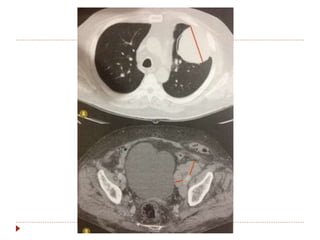

Avaliação de resposta com PET-CT

 PERSIST 1.0

 Validade perante o RECIST: lesões novas

(confirmadas com TC) e não valor de captação.

Avaliação de respostacom PET-CT  Utilizar sempre o mesmo aparelho.  SUV (standart uptake value).  Diferencia tumor viável de necrose/fibrose.  PERSIST 1.0  Validade perante o RECIST: lesões novas (confirmadas com TC) e não valor de captação.